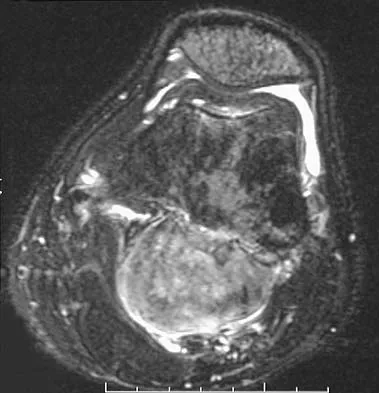

Figures 35a and 35b show the axial T2-weighted and coronal T1-weighted MRI scans of a patient who has enlargement of the right thigh. What is the most likely diagnosis?

Explanation

The images show a large, almost circumferential, mass surrounding the diaphysis of the femur. The intramedullary signal is normal with minimal cortical destruction, both findings that should be abnormal in conventional osteosarcoma and Ewing's sarcoma. There are very low-signal striations representing osteoid formation that would have a sunburst radiographic pattern. This indicates an osteogenic lesion. Myositis ossificans is not indicated because studies would reveal zonal ossification starting in the periphery rather than the more central pattern seen in this patient. This appearance is typical for periosteal osteosarcoma.